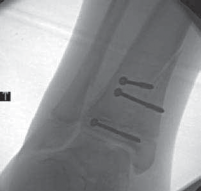

A B C DTECH FIG 2•

Treatment of Salter-Harris type II supination–external rotation (SER) type of fracture with interposed periosteum.

A,B.

Radiographs demonstrate a Salter-Harris type II SER type of fracture gapped anteriorly.

C.

Periosteum (shown in red) is often interposed anteriorly in SER-type Salter-Harris II fractures, which prevents closed reduction.

D.

This periosteum must be carefully extracted from the physeal fracture to obtain anatomic reduction and decrease the chance of premature physeal closure.

TECHNIQUES E F G HTECH FIG 2•

(continued)_E,F. Open reduction was obtained after failed closed reduction due to interposed periosteum in the physeal fracture. Then the fracture was stabilized with two crossed Kirschner wires placed percutaneously. G,H. At 1 year postoperatively the distal tibial physis appears open. The _red arrows

mark the Harris growth line, which is parallel with the physis, demonstrating symmetric growth after injury. This further supports that the tibial physis is open.